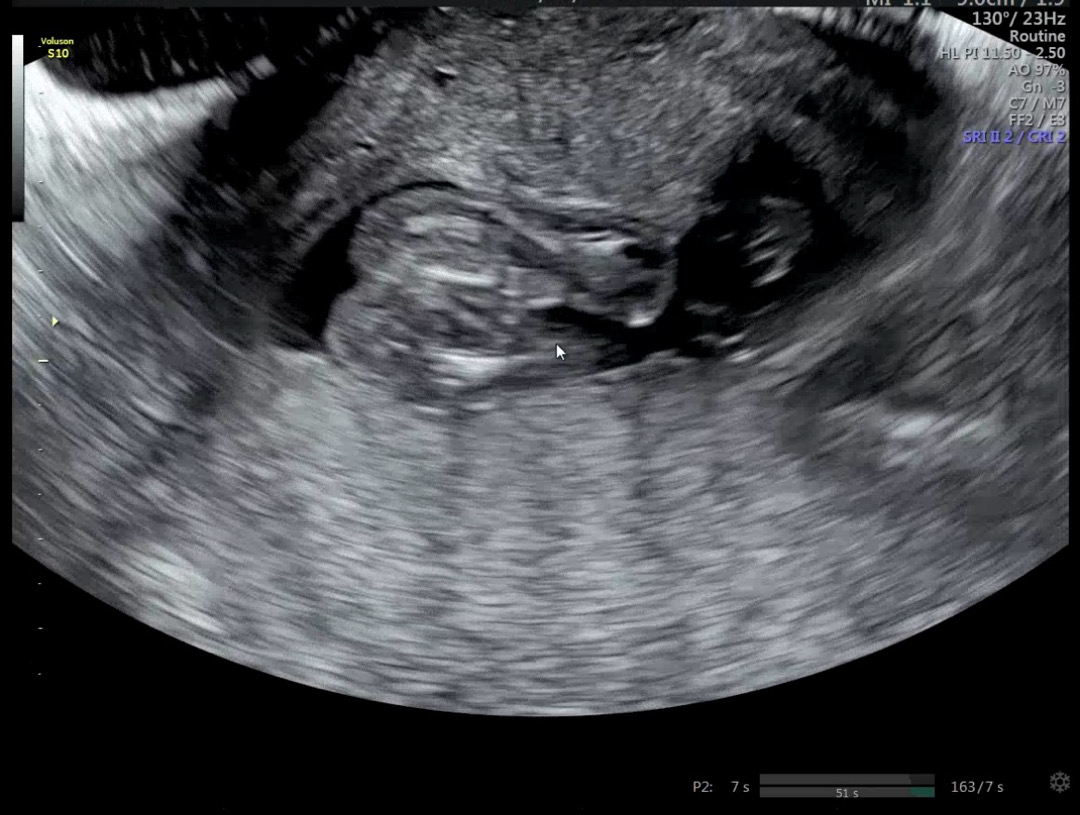

저는 아들인데ㅋ 남편도 반전있기를 바라는 눈치입니다ㅋ 그러나 미사일이 존재감 뿜뿜이라죠ㅋ

남편은 의사가 딸이라고 했는데도 못믿겠다는데..

제발 댓글로 저희 남편 좀 믿게해주세요🙏🏻 의사선생님이 엄마 닮았네요 라고 까지 말했는데 긴가민가 하다면서 .. 나참🥺 확실해지면 그때 좋아할거라고....후.. 16주5일차 입니다

16주면 바뀔것도없죠 뭐,,,

아들은 16주면 툭튀어나와있어요 ㅋㅋㅋ 애매하고 그런거 없어요..제가 그랬거든요 ㅋㅋㅋ